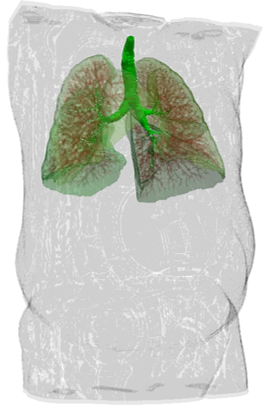

Exemples de segmentation par IA

système pulmonaire et vaisseaux

Depuis un scanner - Chaque landmak est indépendant.